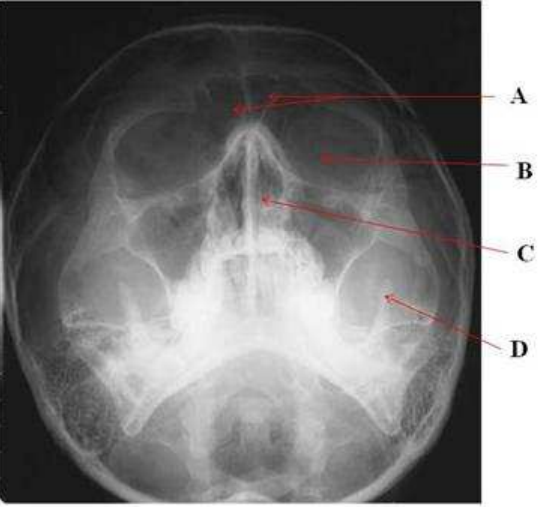

64.下圖中,各部位名稱何者正確?

(A)A:sphenoid sinus (B)B:maxillary sinus (C)C:nasal septum (D)D:condyle head